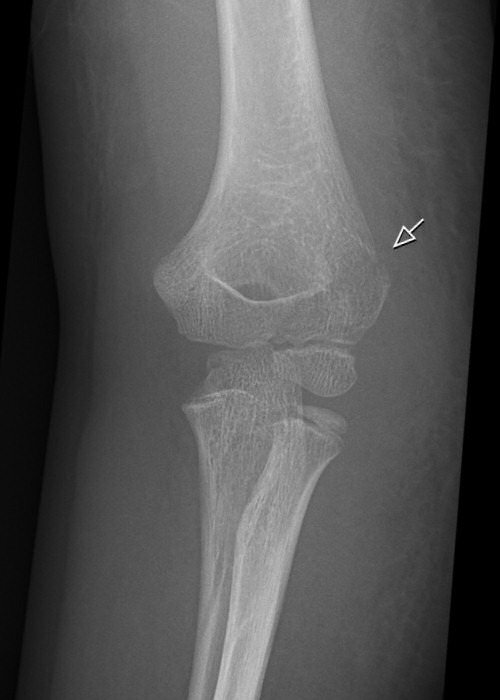

Fraktur på laterala humerusepikondylen, behandlades icke-kirurgiskt

- Innan röntgenundersökning så anamnes, inspektion, palpation och distalstatus. Distalstatus är extra viktigt vid armbågsskador då både nerver och blodkärl kan skadas.

- Röntgenundersökning, helst utan gips för att få bättre bilder.

Icke-kirurgisk behandling:

- Om alla 3 av: [1]

- ≤ 2 mm diastas

- ≤ 1 mm nivåskillnad i ledyteplanet

- ≤ 20° dorsalbockning